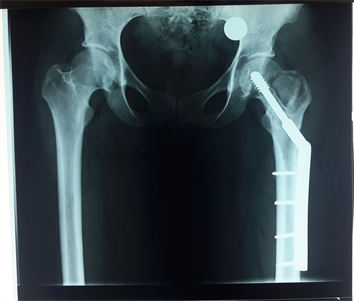

Figure 3. X-ray after curettage, filling by a graft of the iliac crest and stabilization by DHS.

A biopsy was performed and the diagnosis of GCT was made and classified as stage II of Enneking. We proceeded, by a Watson-Jones approch, to a careful curettage with cauterization of the bone walls with the electric scalpel. The residual cavity was filled by a tri cortical graft of the iliac crest and a stabilization by dynamic hip screw was made (Figure 3).